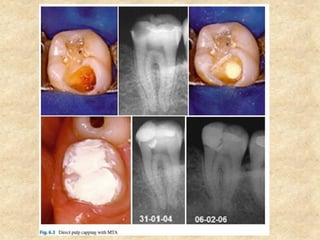

1. Pulp Capping:

• MTA has been proposed as a potential medicament for capping of pulps

with reversible pulpitis because of its excellent tissue compatibility. It is

much superior to the routinely used calcium hydroxide based on the tissue

reaction and the amount and type of dentin bridge formed.

• Calcium hydroxide is associated with tissue necrosis and inflammation

during the initial period of placement but no such inflammation or

necrosis was seen in the pulp tissue adjacent to MTA.

• With MTA, dentin bridge after pulp capping was seen at about 1 week

which steadily increased in length and thickness within 3 months of

capping whereas following pulp capping with calcium hydroxide, the

dentin bridge was less consistent and had numerous tunnel defects.

• Since there is no pulpal necrosis, pulp tissue heals faster with MTA.

Aeinehchi et al in 2003 reported a 0.28 mm thick dentin bridge by 2

months which increased to 0.43 mm by 6 months. The dentin bridge

formed with calcium hydroxide was only 0.15 mm by 6 months.

1. Pulp Capping: •MTA has been proposed as a potential medicament for capping of pulps with reversible pulpitis because of its excellent tissue compatibility. It is much superior to the routinely used calcium hydroxide based on the tissue reaction and the amount and type of dentin bridge formed. • Calcium hydroxide is associated with tissue necrosis and inflammation during the initial period of placement but no such inflammation or necrosis was seen in the pulp tissue adjacent to MTA. • With MTA, dentin bridge after pulp capping was seen at about 1 week which steadily increased in length and thickness within 3 months of capping whereas following pulp capping with calcium hydroxide, the dentin bridge was less consistent and had numerous tunnel defects. • Since there is no pulpal necrosis, pulp tissue heals faster with MTA. Aeinehchi et al in 2003 reported a 0.28 mm thick dentin bridge by 2 months which increased to 0.43 mm by 6 months. The dentin bridge formed with calcium hydroxide was only 0.15 mm by 6 months.